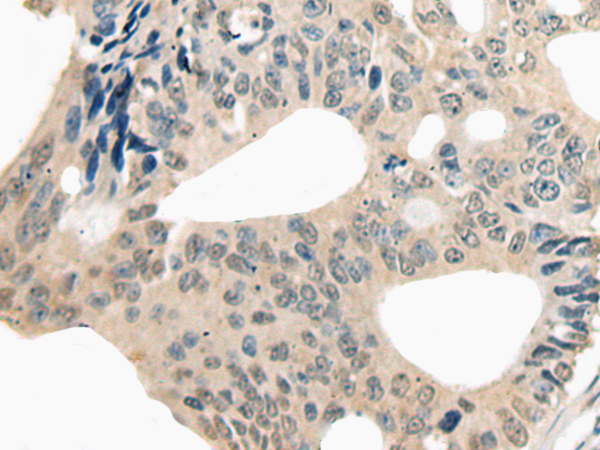

IHC positive control: |

Human colorectal cancer |

IHC Recommend dilution: |

20-100 |